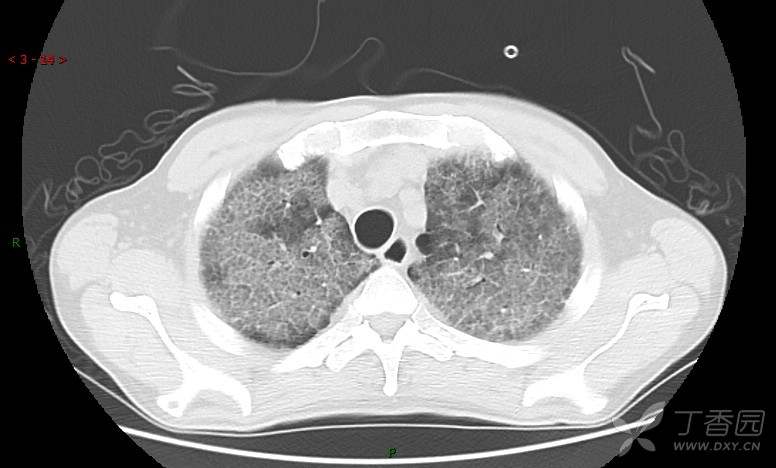

地图+铺路石征=PAP?那升高的CEA怎么说(病例3连发,附其他2例链接)

患者男,42岁,咳嗽半年余,加重伴憋喘2月余。

肺内弥漫性网状结节影,PET-CT却无阳性病灶,这是?(附其他2例链接)